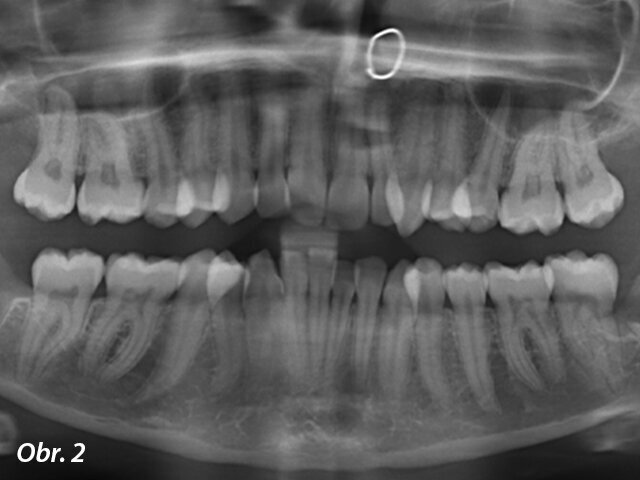

Na rentgenu se ukázalo, že struktura a morfologie kořenů je normální. V místě extrahovaného zubu 38 byly nalezeny pozůstatky kořene (obr. 2). Kefalometrická analýza odhalila I. třídu skeletálního modelu s lehce zvýšenou proklinací horních a dolních špičáků (obr. 3).